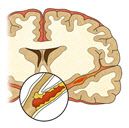

◇ 뇌졸중은 혈관이 막히거나 터져 뇌 조직이 손상되는 질환

뇌졸중은 혈관이 막히거나 터져서 뇌 조직이 손상되는 질환이다. 혈관이 막혀 뇌가 손상되면 ‘뇌경색’, 혈관이 터져서 뇌가 손상되면 ‘뇌출혈’로 분류된다. 뇌경색이 전체 뇌졸중의 80%를 차지한다. 뇌경색은 동맥경화(혈관 벽 내부에 지방 성분과 염증 세포가 쌓여 동맥이 딱딱하게 굳어지는 상태)가 주원인이 되어 발생한다. 뇌혈관이 터져 출혈이 생기는 출혈성 뇌졸중은 20% 정도 된다. 뇌출혈 중에서는 고혈압에 의해 손상된 뇌혈관이 파열되는 뇌내출혈과 뇌혈관에 생긴 꽈리 모양의 동맥류가 터져 생기는 지주막하 출혈 등이 있다.